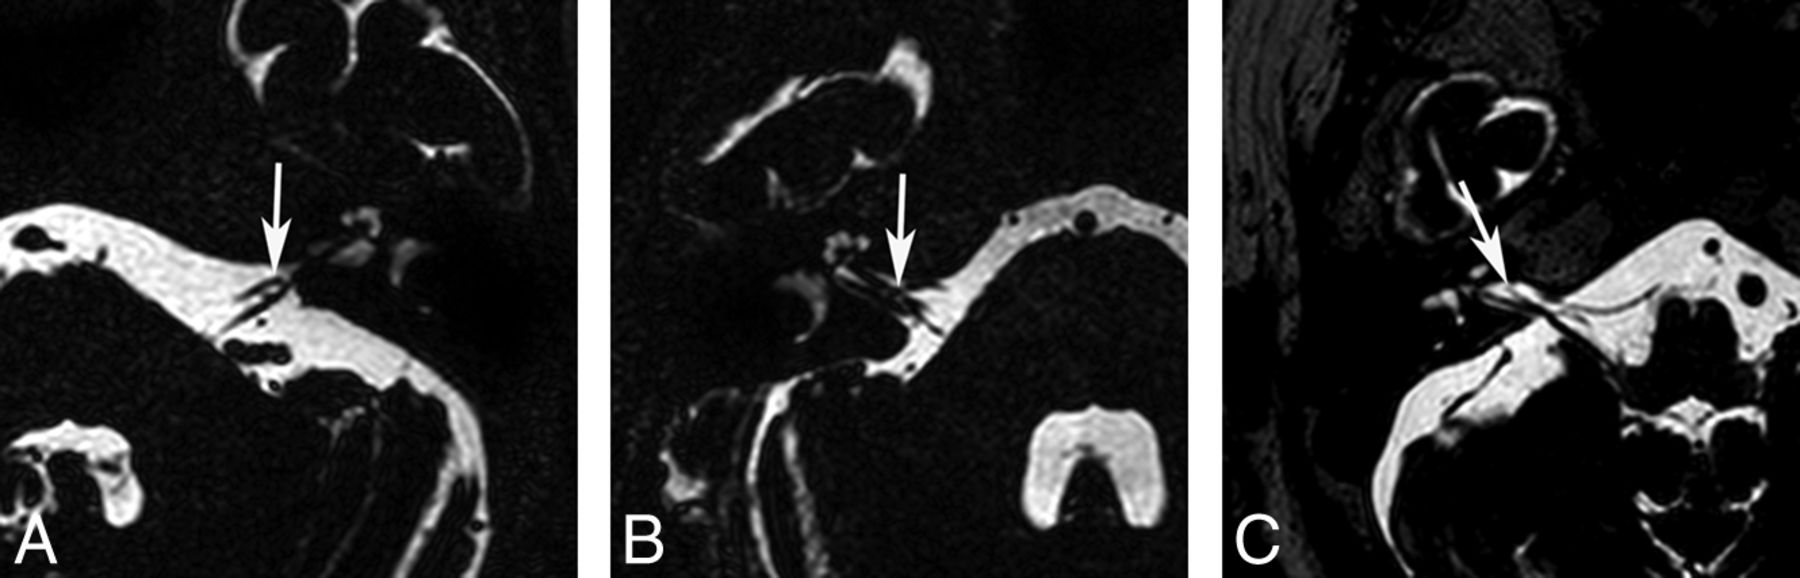

Two neuroradiologists blinded to the clinical findings of the subjects evaluated the neurovascular structures of the IAC and CPA on axial 3D T2-VISTA images and sagittal and/or coronal reconstructed images and made final decisions in consensus. First, the type of AICA loop of all study subjects was determined by using the Chavda classification13 as follows: type I, the AICA loop lying within the CPA but not entering the IAC (Fig 1A and On-line Fig 1A); type II, the AICA loop entering the IAC but not extending >50% of the length of the IAC (Fig 1B and On-line Fig 1B); and type III, the AICA loop extending into >50% of the IAC (Fig 1C and On-line Fig 1C). Second, the type of neurovascular contact was classified into the following 3 categories: type I, no neurovascular contact (Fig 2A and On-line Fig 2A); type II, neurovascular contact present at the cochleovestibular nerve complex but without angulation/indentation of the nerve (Fig 2B and On-line Fig 2B); and type III, neurovascular compression causing cochleovestibular nerve angulation/indentation (Fig 2C and On-line Fig 2C).12 In addition, the presence of neurovascular contact with arterial structures other than the AICA was assessed.

Neurovascular contact types between the AICA and the cochleovestibular nerve. A, A type I neurovascular contact shows no neurovascular contact (arrow). B, A type II neurovascular contact shows contact (arrow) between the AICA and the cochleovestibular nerve without angulation/indentation of the nerve. C, A type III neurovascular contact shows angulation/indentation (arrow) of the cochleovestibular nerve by the AICA loop.